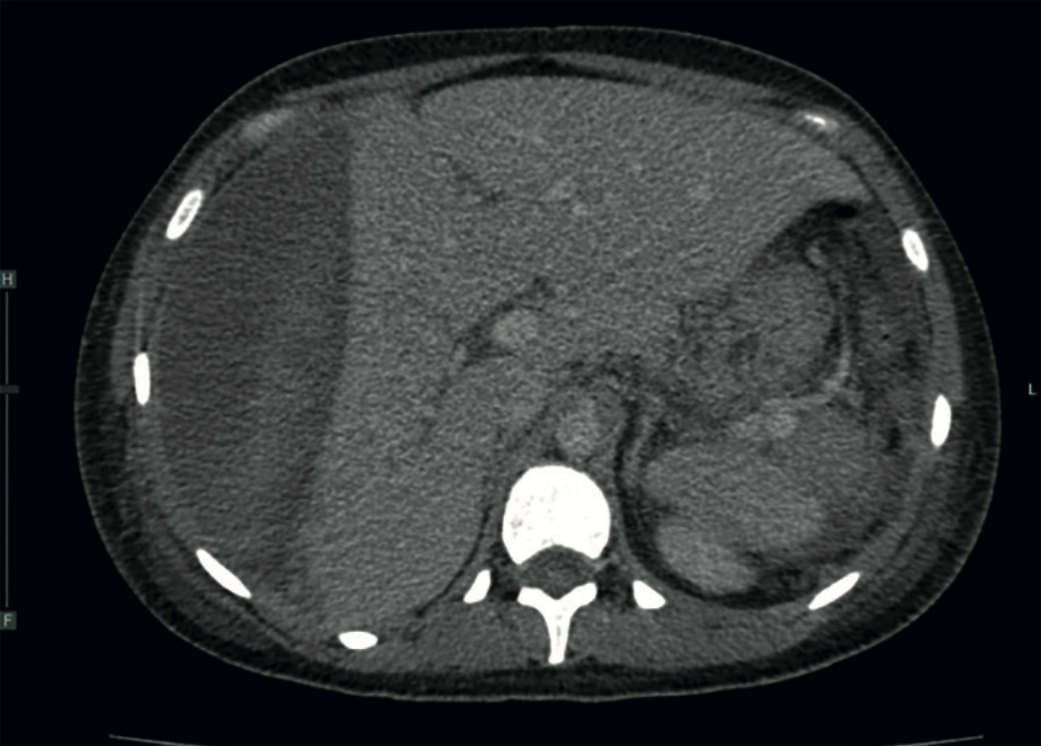

El ultrasonido y la tomografía axial computada confirmaron el hematoma subcapsular hepático que afectaba el 50% de la superficie glandular (Figura 1). La resonancia magnética sugirió un edema cerebral compatible con síndrome de encefalopatía posterior reversible (PRES). Ante el diagnóstico de hematoma hepático subcapsular y el alto riesgo de avance, se procedió a la laparotomía exploradora. Se encontró un hemoperitoneo de 200 mL y un hematoma subcapsular del 50%. Se decidió el empaquetamiento hepático y la colocación de drenajes. De manera complementaria, el radiólogo intervencionista llevó a cabo una embolización selectiva de la arteria hepática común mediante la aplicación de 5 mL de espuma hemostática, vía cateterismo del tronco celiaco (Figura 2). Luego del procedimiento, la paciente evolucionó hacia la estabilidad hemodinámica, con logro de una extubación satisfactoria y alta al servicio de ginecología al día siguiente de la embolización. Al sexto día de estancia hospitalaria la paciente se reportó consciente, orientada y con mejoría sustancial del perfil hepático (AST 420 U/L, ALT 1139 U/L) y recuperación de la función renal.

<strong>Figura 2</strong>

Figura 2. Angiografía por sustracción digital. Se observa el cateterismo selectivo de la arteria hepática común a través de un acceso femoral. Se identifica la anatomía arterial del hígado con una adecuada perfusión parenquimatosa inicial.